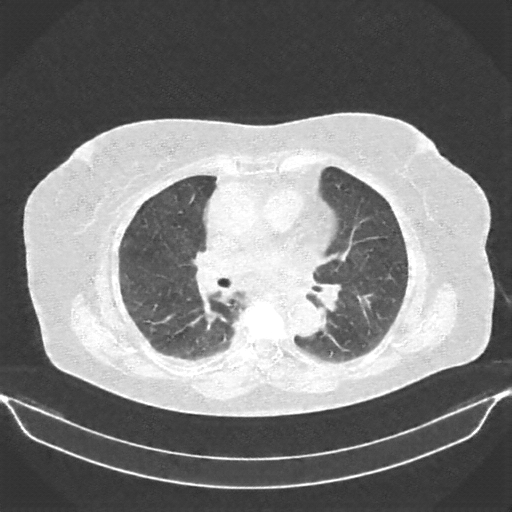

Targeted Slice 70 - Lung Window Analysis (Generated vs Real Venous)

0.660

Lung SSIM

118.4

Lung RMSE

51.5

Lung MAE

Average Lung Window Metrics Across All Slices (161 slices) - Generated vs Real Venous

0.663

Lung SSIM (Avg)

109.6

Lung RMSE (Avg)

49.1

Lung MAE (Avg)

Original NATIVE CT scan (input)

No window - Raw intensity values

Lung window (WL -600, WW 1500 β†’ Low βˆ’1350, High +150)